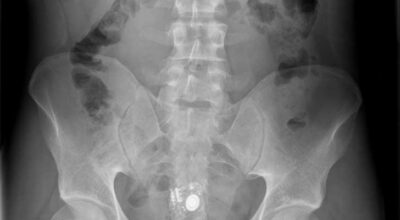

Esta recopilación de imágenes recoge alguna de las situaciones más estrambóticas que se han podido dar en una sala de rayos X. Todas ellas tienen algo en común: Son objetos extraños para el cuerpo humano que, de alguna manera han encontrado una vía de entrada, pero se han perdido a la hora de encontrar la de salida.

Muñecas de juguete descabezadas, botellas, armas, frascos, botes de plástico, teléfonos y hasta una cinta de casete pueden encontrarse en esa suerte de “punto limpio” al que ha quedado reducido el interior de los afectados.